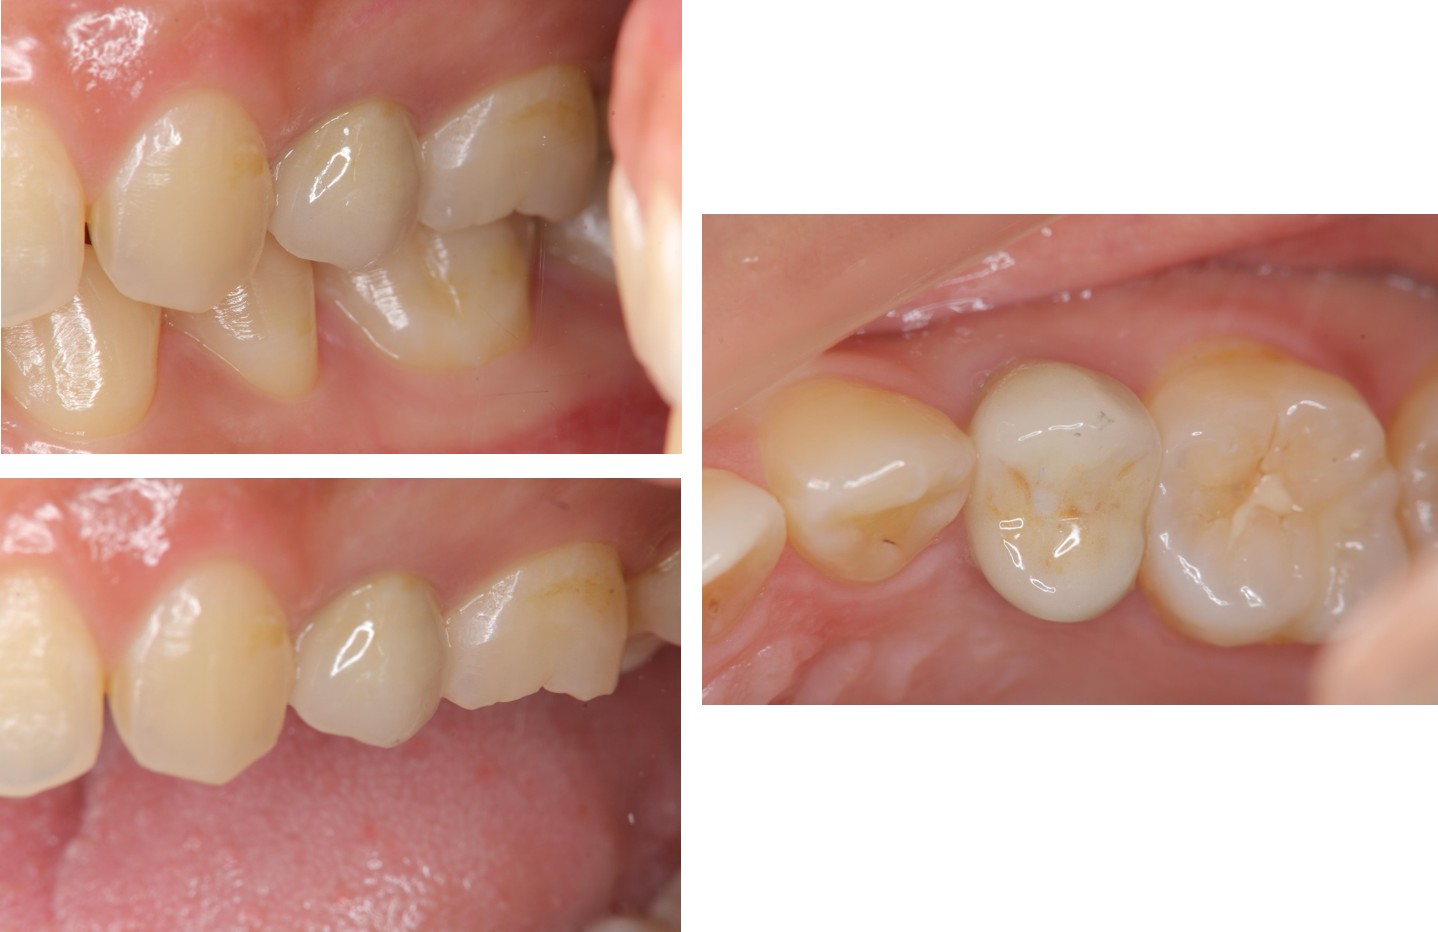

治療後,牙周咬合良好

治療後,密合度良好

術前、術後比較